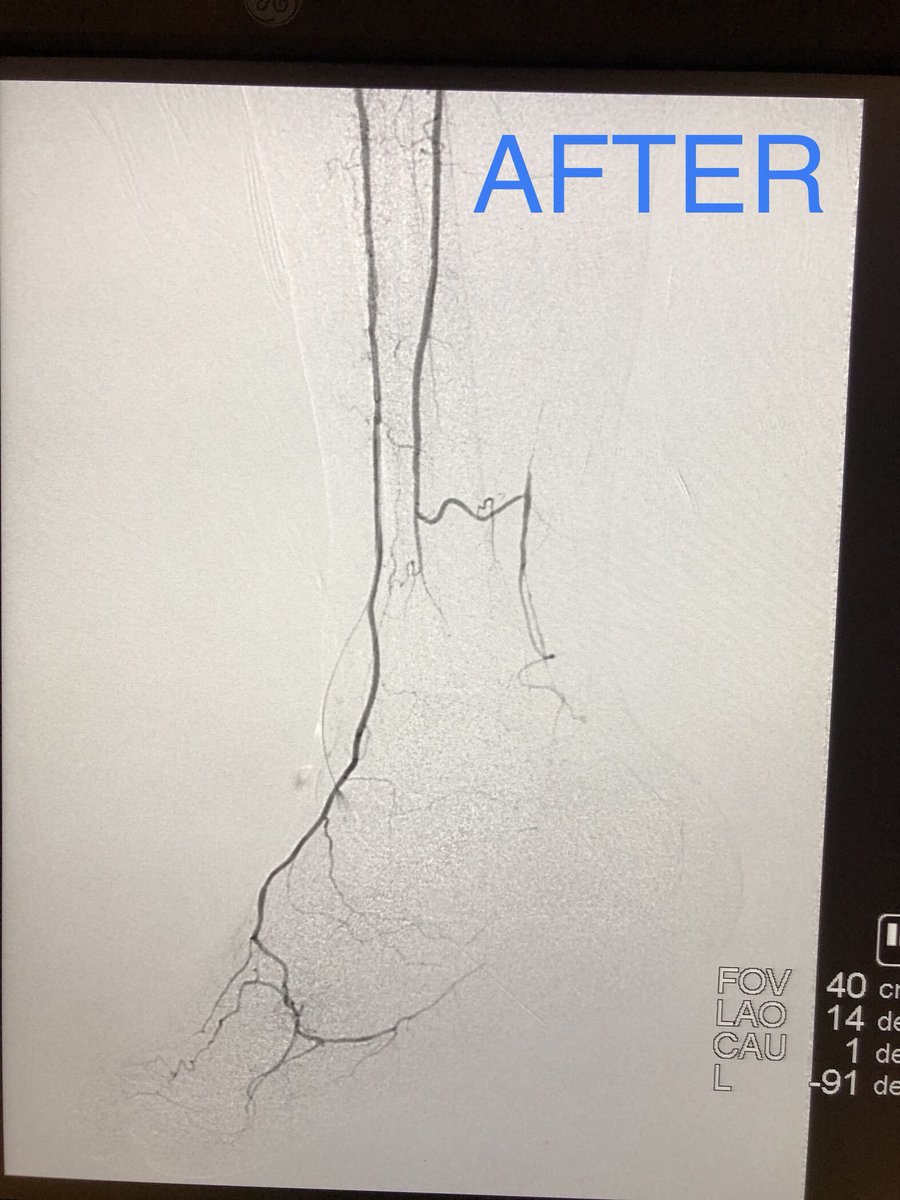

What to do when you can’t get through a distal anastomotic stricture of a thrombosed fem-pop bypass despite lysis? Just open up his native SFA! Special thanks to my fellow, Yusuf @yhkarrar ! UICOMP Radiology SIR RFS Society of Interventional Radiology @

What to do when you can’t get through a distal anastomotic stricture of a thrombosed fem-pop bypass despite lysis? Just open up his native SFA! Special thanks to my fellow, Yusuf @yhkarrar ! <a href="/UICOMPRadiology/">UICOMP Radiology</a> <a href="/SIRRFS/">SIR RFS</a> <a href="/SIRspecialists/">Society of Interventional Radiology</a> @